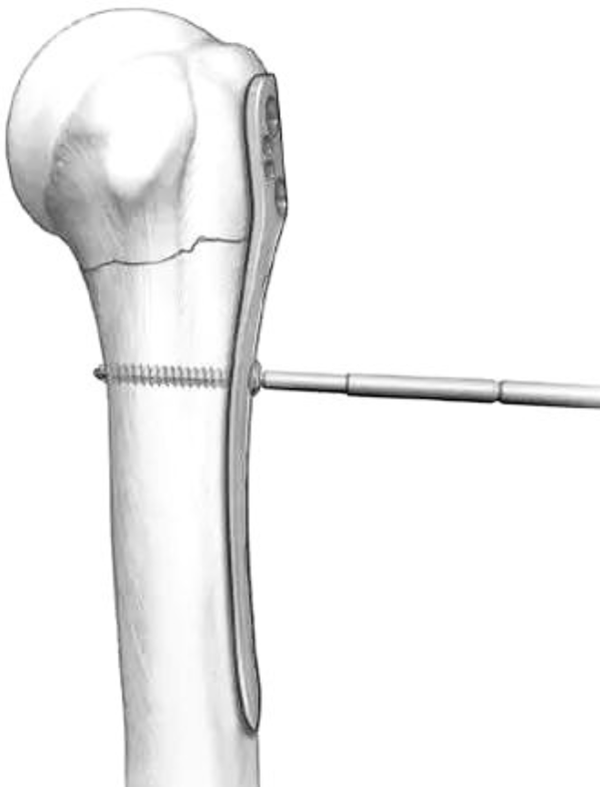

(4)解剖锁钉板固定

肱骨近端锁定钢板放置在结节间沟偏大结节一侧(结节间沟外侧),在置板前可先将“8”字缝合钢丝预置,再固定钢板。

钢板理想的位置是大结节上缘下5mm,并位于结节间沟外侧2-4mm。

解剖锁定板加钢丝张立带双套固定达到解剖复位,坚强固定,早期功能锻炼的目的。

(5)由于胸大肌的牵拉,肱骨干通常都向内移位。

图14 可以先将钢板固定在肱骨头外侧面,而此时骨干可能仍然存在向内移位,在骨折线远端的第一个螺钉孔置入一枚3.5mm皮质骨螺钉将肱骨干向外提拉复位

图15 通过提拉,达到解剖复位